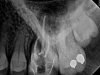

In general, for infections that warrant systemic antibiotic prescriptions, a systematic approach to prescription is essential. Clinicians should start by prescribing the narrowest-spectrum drug possible for the shortest duration in order to specifically target the pathogenic species while minimizing effects on normal flora. The best choices for initial treatment in the non-penicillin-allergic population are penicillin VK and amoxicillin. For infections that do not resolve with these medications within 48 hours, clavulanic acid in combination with amoxicillin (Augmentin®) can be considered as an alternative drug. Alternatively, metronidazole can be added to a beta-lactam regimen if the infection does not resolve. In penicillin-allergic patients, azithromycin or a cephalosporin should be used as first-line agents (Figure 2 through Figure 4). Current clinical guidelines advise that cephalosporins should only be used if the patient does not have a history of anaphylaxis or angioedema with penicillin due to potential cross-allergenicity between these two drugs.26 If an infection is unresponsive to these first- and second-line choices, clindamycin should be considered as the final, broad-spectrum option (Figure 5).10